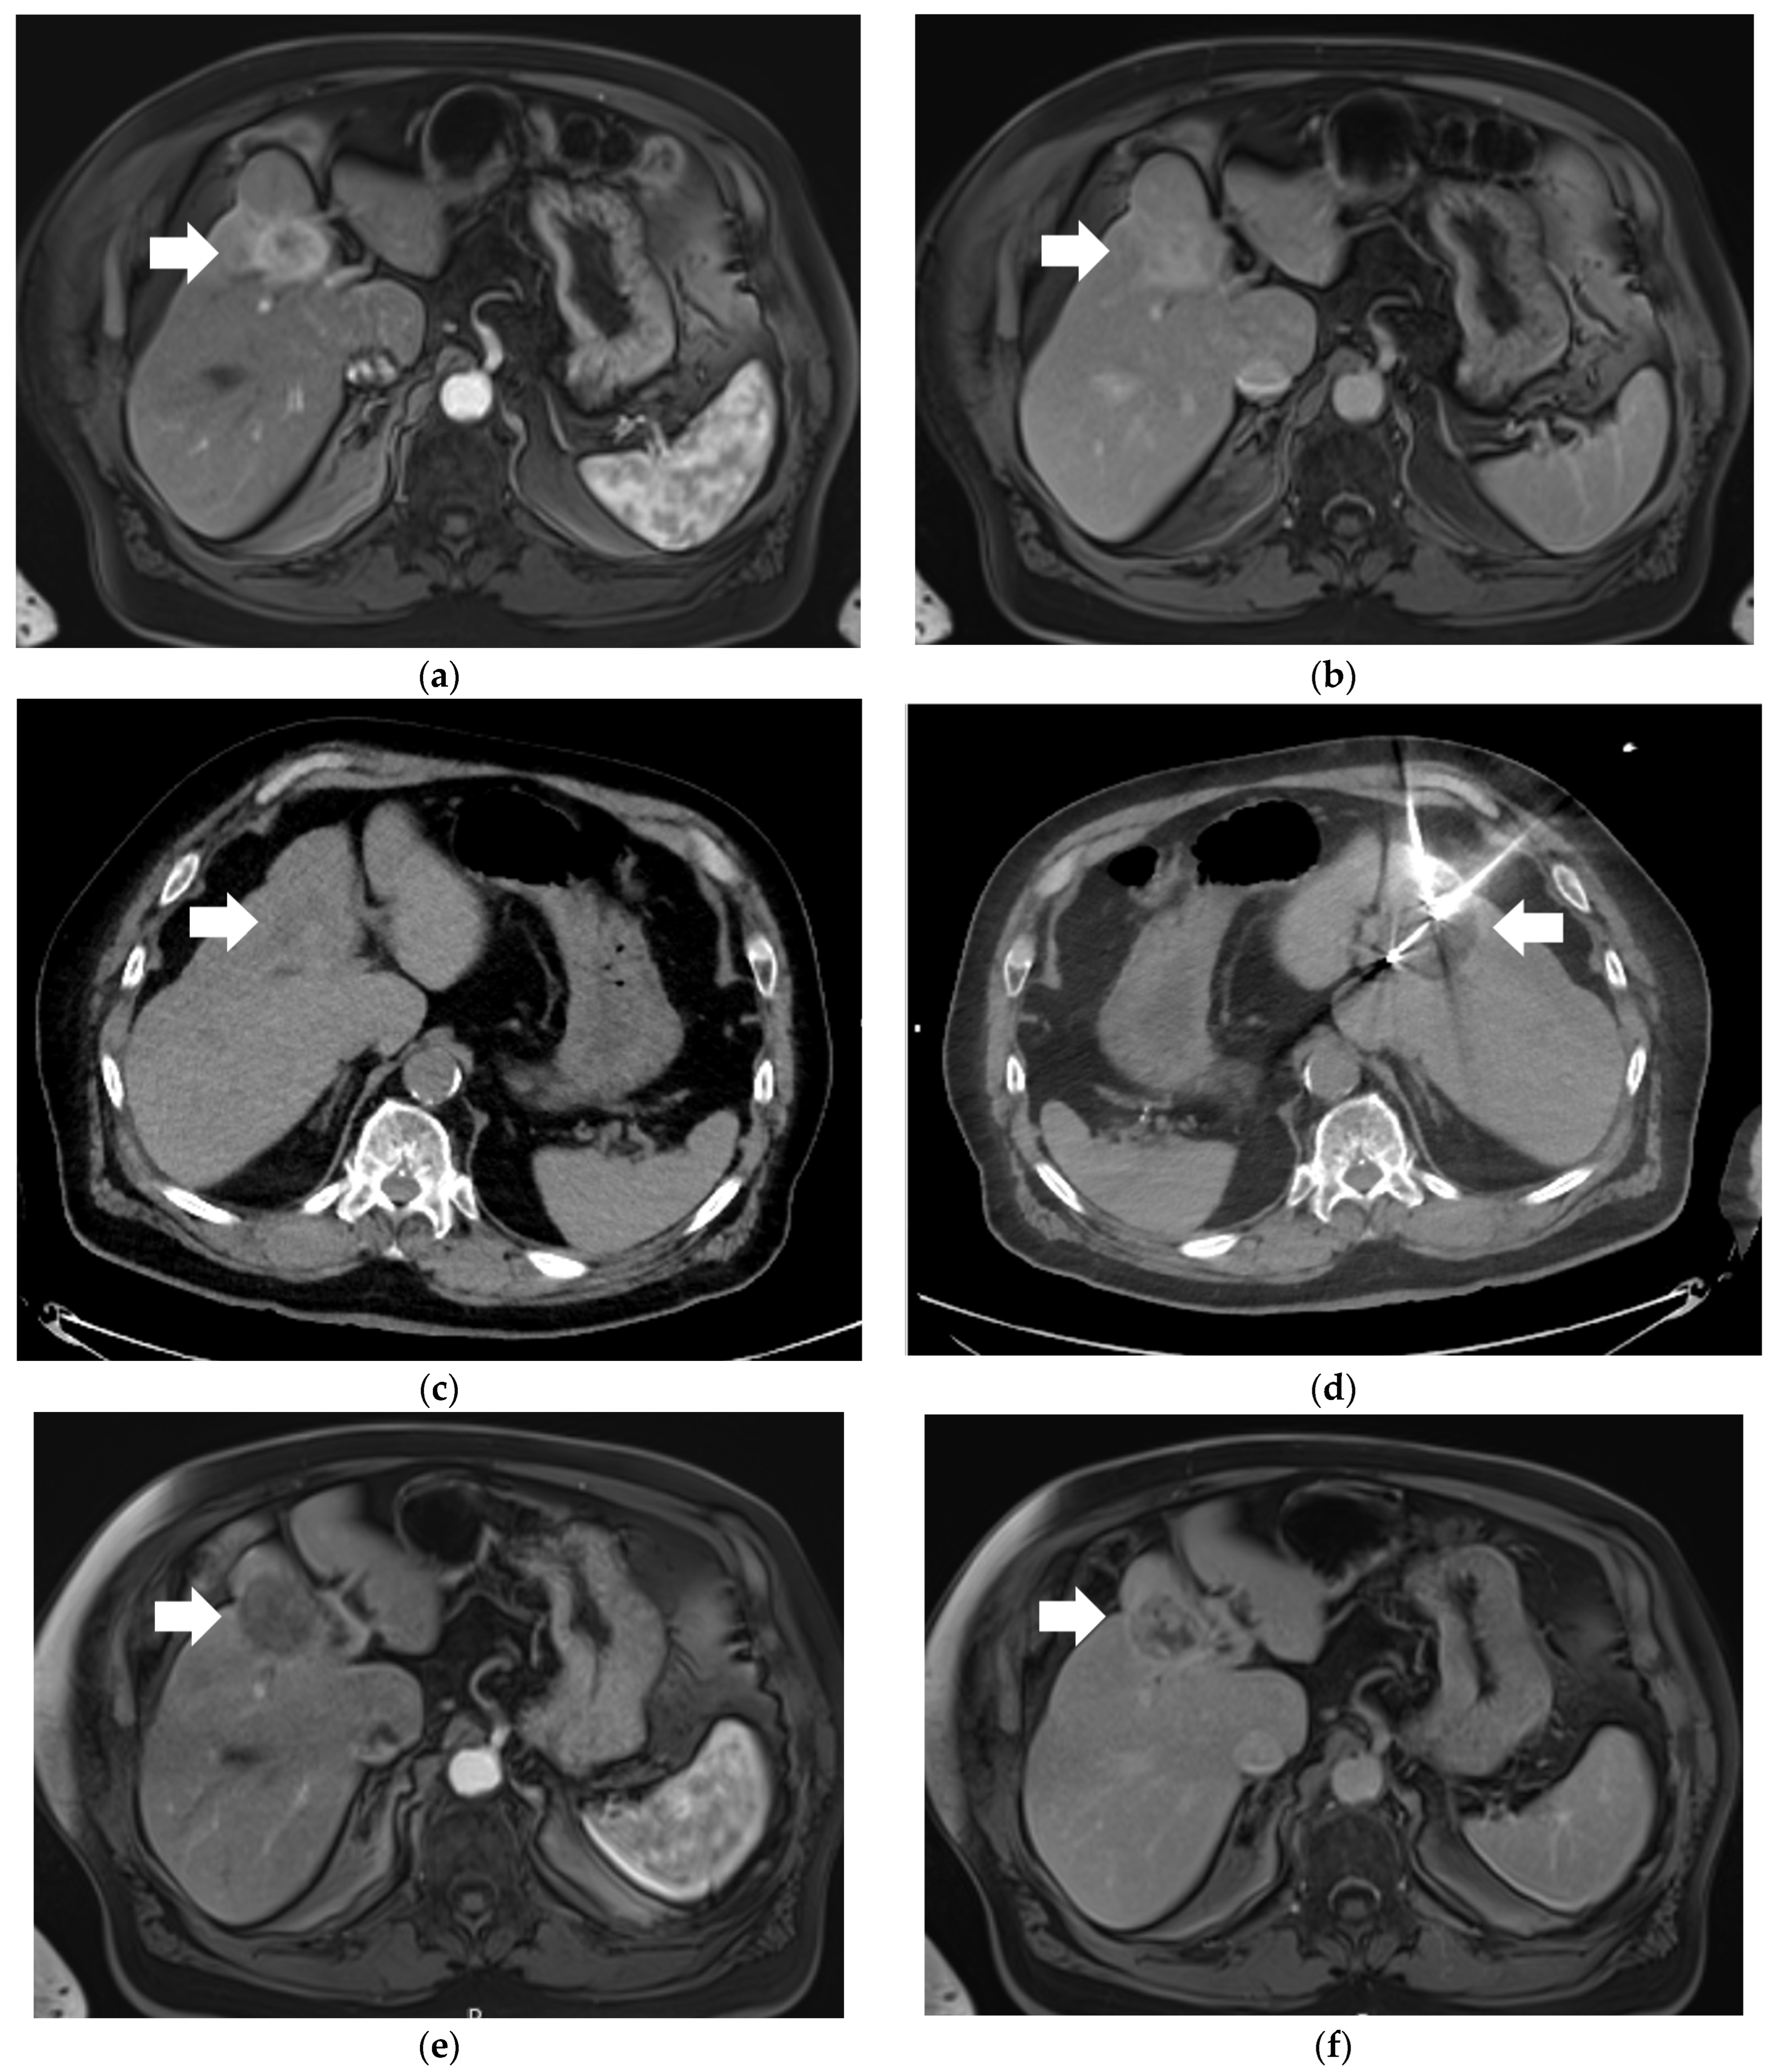

Figure 1.

77-year-old male with a 3.7 cm intrahepatic cholangiocarcinoma (iCCA) in Segment 4A of the liver who underwent percutaneous cryoablation. (a) Selected arterial-phase contrast-enhanced T1-weighted magnetic resonance imaging (MRI) image demonstrating avid enhancement of the iCCA (arrow) compared to background liver parenchyma. (b) Selected delayed-phase contrast-enhanced T1-weighted MRI image demonstrating persistently elevated enhancement of the iCCA (arrow) relative to background liver. (c) Selected pre-procedural non-contrast axial CT image demonstrating the iCCA (arrow) as hypodense relative to background liver parenchyma. (d) Selected intra-procedural non-contrast axial CT image demonstrating two of a total of three cryoablation probes positioned within the iCCA, as well as associated “ice ball” (arrow). (e) Selected 1-month post-cryoablation arterial-phase contrast-enhanced T1-weighted MRI image demonstrating absence of previously seen tumoral enhancement. (f) Selected 1-month post-cryoablation delayed-phase contrast-enhanced T1-weighted MRI image demonstrating absence of previously seen tumoral enhancement.